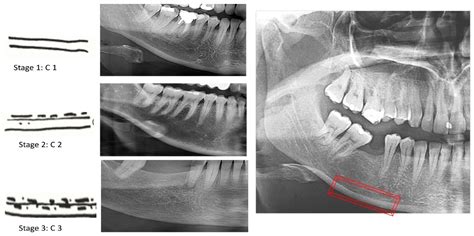

• Wisdom Tooth Assessment: It is the standard procedure to check the alignment and depth of impacted third molars.

Once the images are generated, your dentist will examine them for any abnormalities. Because the image is an orthopantomogram, it flattens the curved jaw into a two-dimensional plane. This allows the dentist to compare the symmetry of the left and right sides of your mouth. They will look for:

• The presence and eruption status of wisdom teeth.